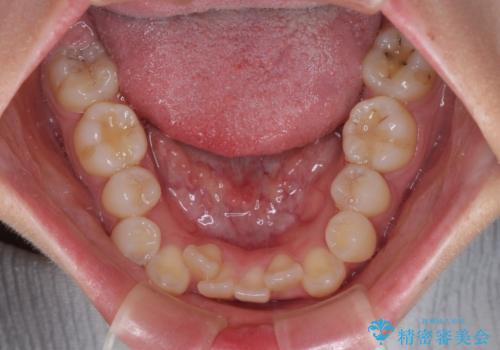

- 下の前歯のデコボコと、口元の突出感を改善したいと来院された患者様です。

上下左右の第一小臼歯を抜歯して、目立ちにくいワイヤー装置で矯正を行いました。

上下の保定用マウスピースの他に、デコボコの強かった下顎前歯にはワイヤーで保定をしています。